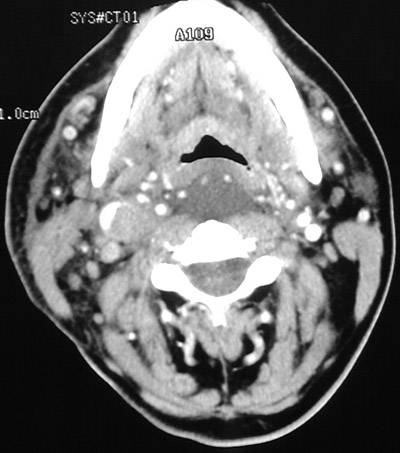

The head and neck CT scans with contrast above and below demonstrate thrombus filling and distending the internal jugular vein, with a rim of bright contrast. This thrombus extended from the superior vena cava.